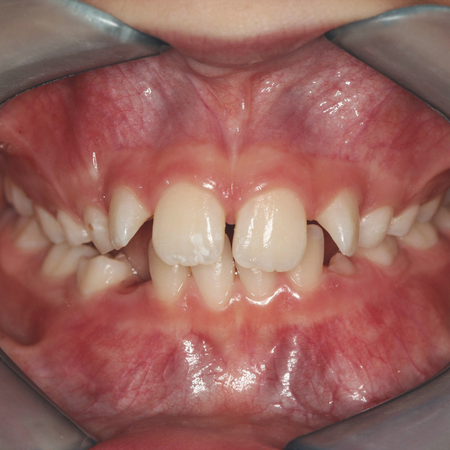

Expansor de Haas na interceptação da erupção ectópica de primeiro molar permanente superior

OBJETIVO: O objetivo deste artigo é apresentar um caso clínico de uma paciente, com 7 anos de idade, que fora submetido a expansão maxilar com o aparelho de Haas e, após 10 meses de acompanhamento, foi identificada erupção ectópica do primeiro molar permanente superior direito, por meio de uma radiografia panorâmica. RELATO DO CASO: O tratamento proposto foi usar o mesmo expansor para desimpactar o molar ectópico. O aparelho foi removido e soldou-se ao anel do segundo molar decíduo...

The use of a Haas expander to intercept an ectopic eruption of a maxillary permanent first molar

OBJECTIVE: The aim of this article is to present a clinical case of a 7-year-old patient who underwent maxillary expansion with the Haas expander and, after 10 months of follow-up, ectopic eruption of the upper right permanent first molar was identified using a panoramic radiograph. CASE REPORT: The proposed treatment was to use the same expander to disimpact the ectopic molar. The appliance was removed and a rigid wire extension was soldered to the ring of the deciduous second molar, with a...